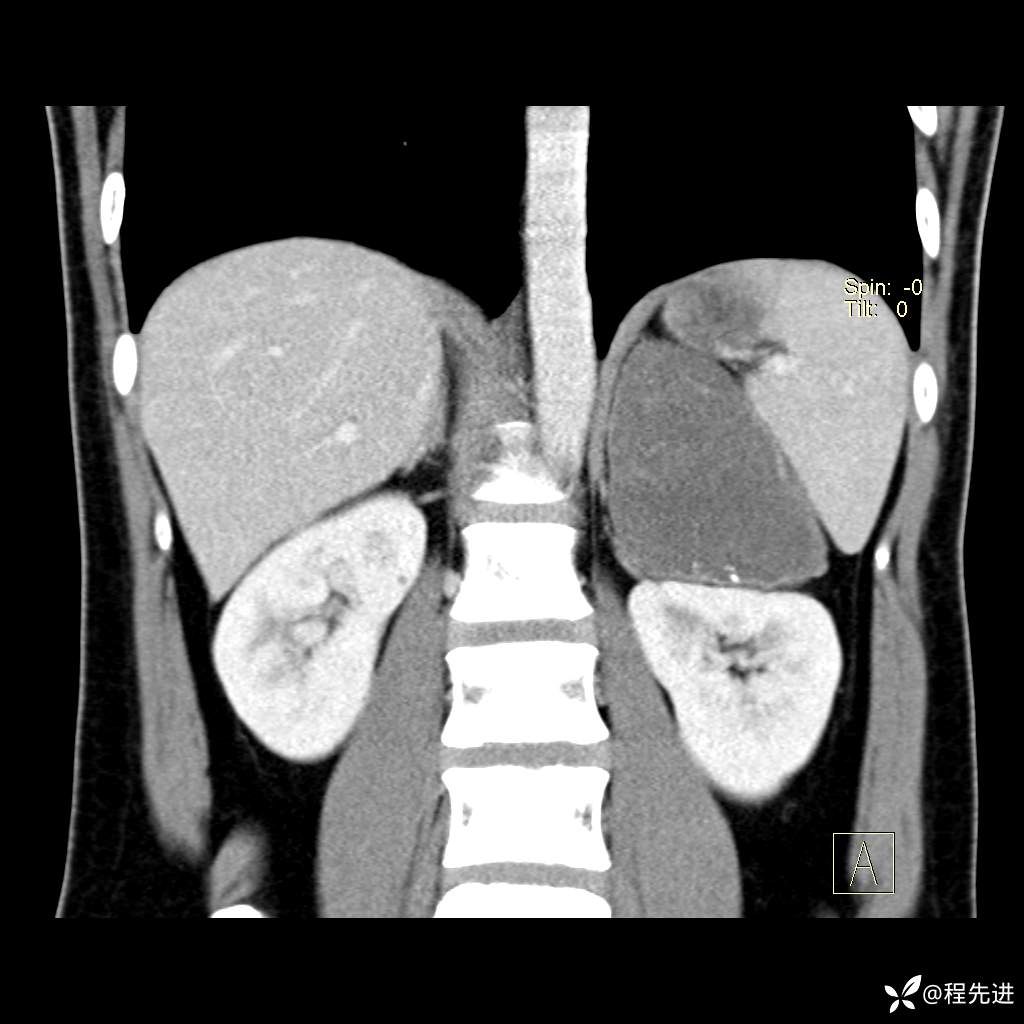

【腹盆】特别精彩病例|体检发现的左侧腹膜后占位期待您的精彩解读

患者年龄:25岁

简要病史:体检发现

CT平扫:(CT值:平扫,27HU,动脉期,27HU,门静脉期,31HU,平衡期,32HU)

冠状位重建: